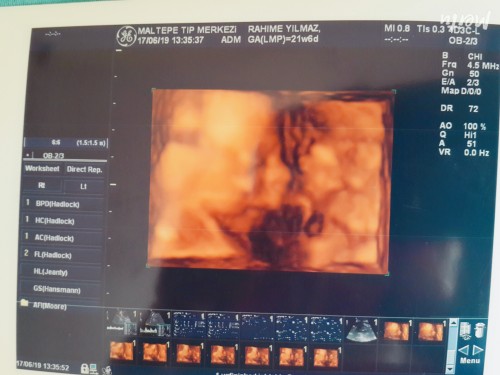

Evet kızlar ultrason fotosunu haftası ile birlikte paylaşır misiniz merak ediyorum hangi haftada nasıl gözüktüğünü :happy: teşekkürler

Bu da benim prensessimm 23+1